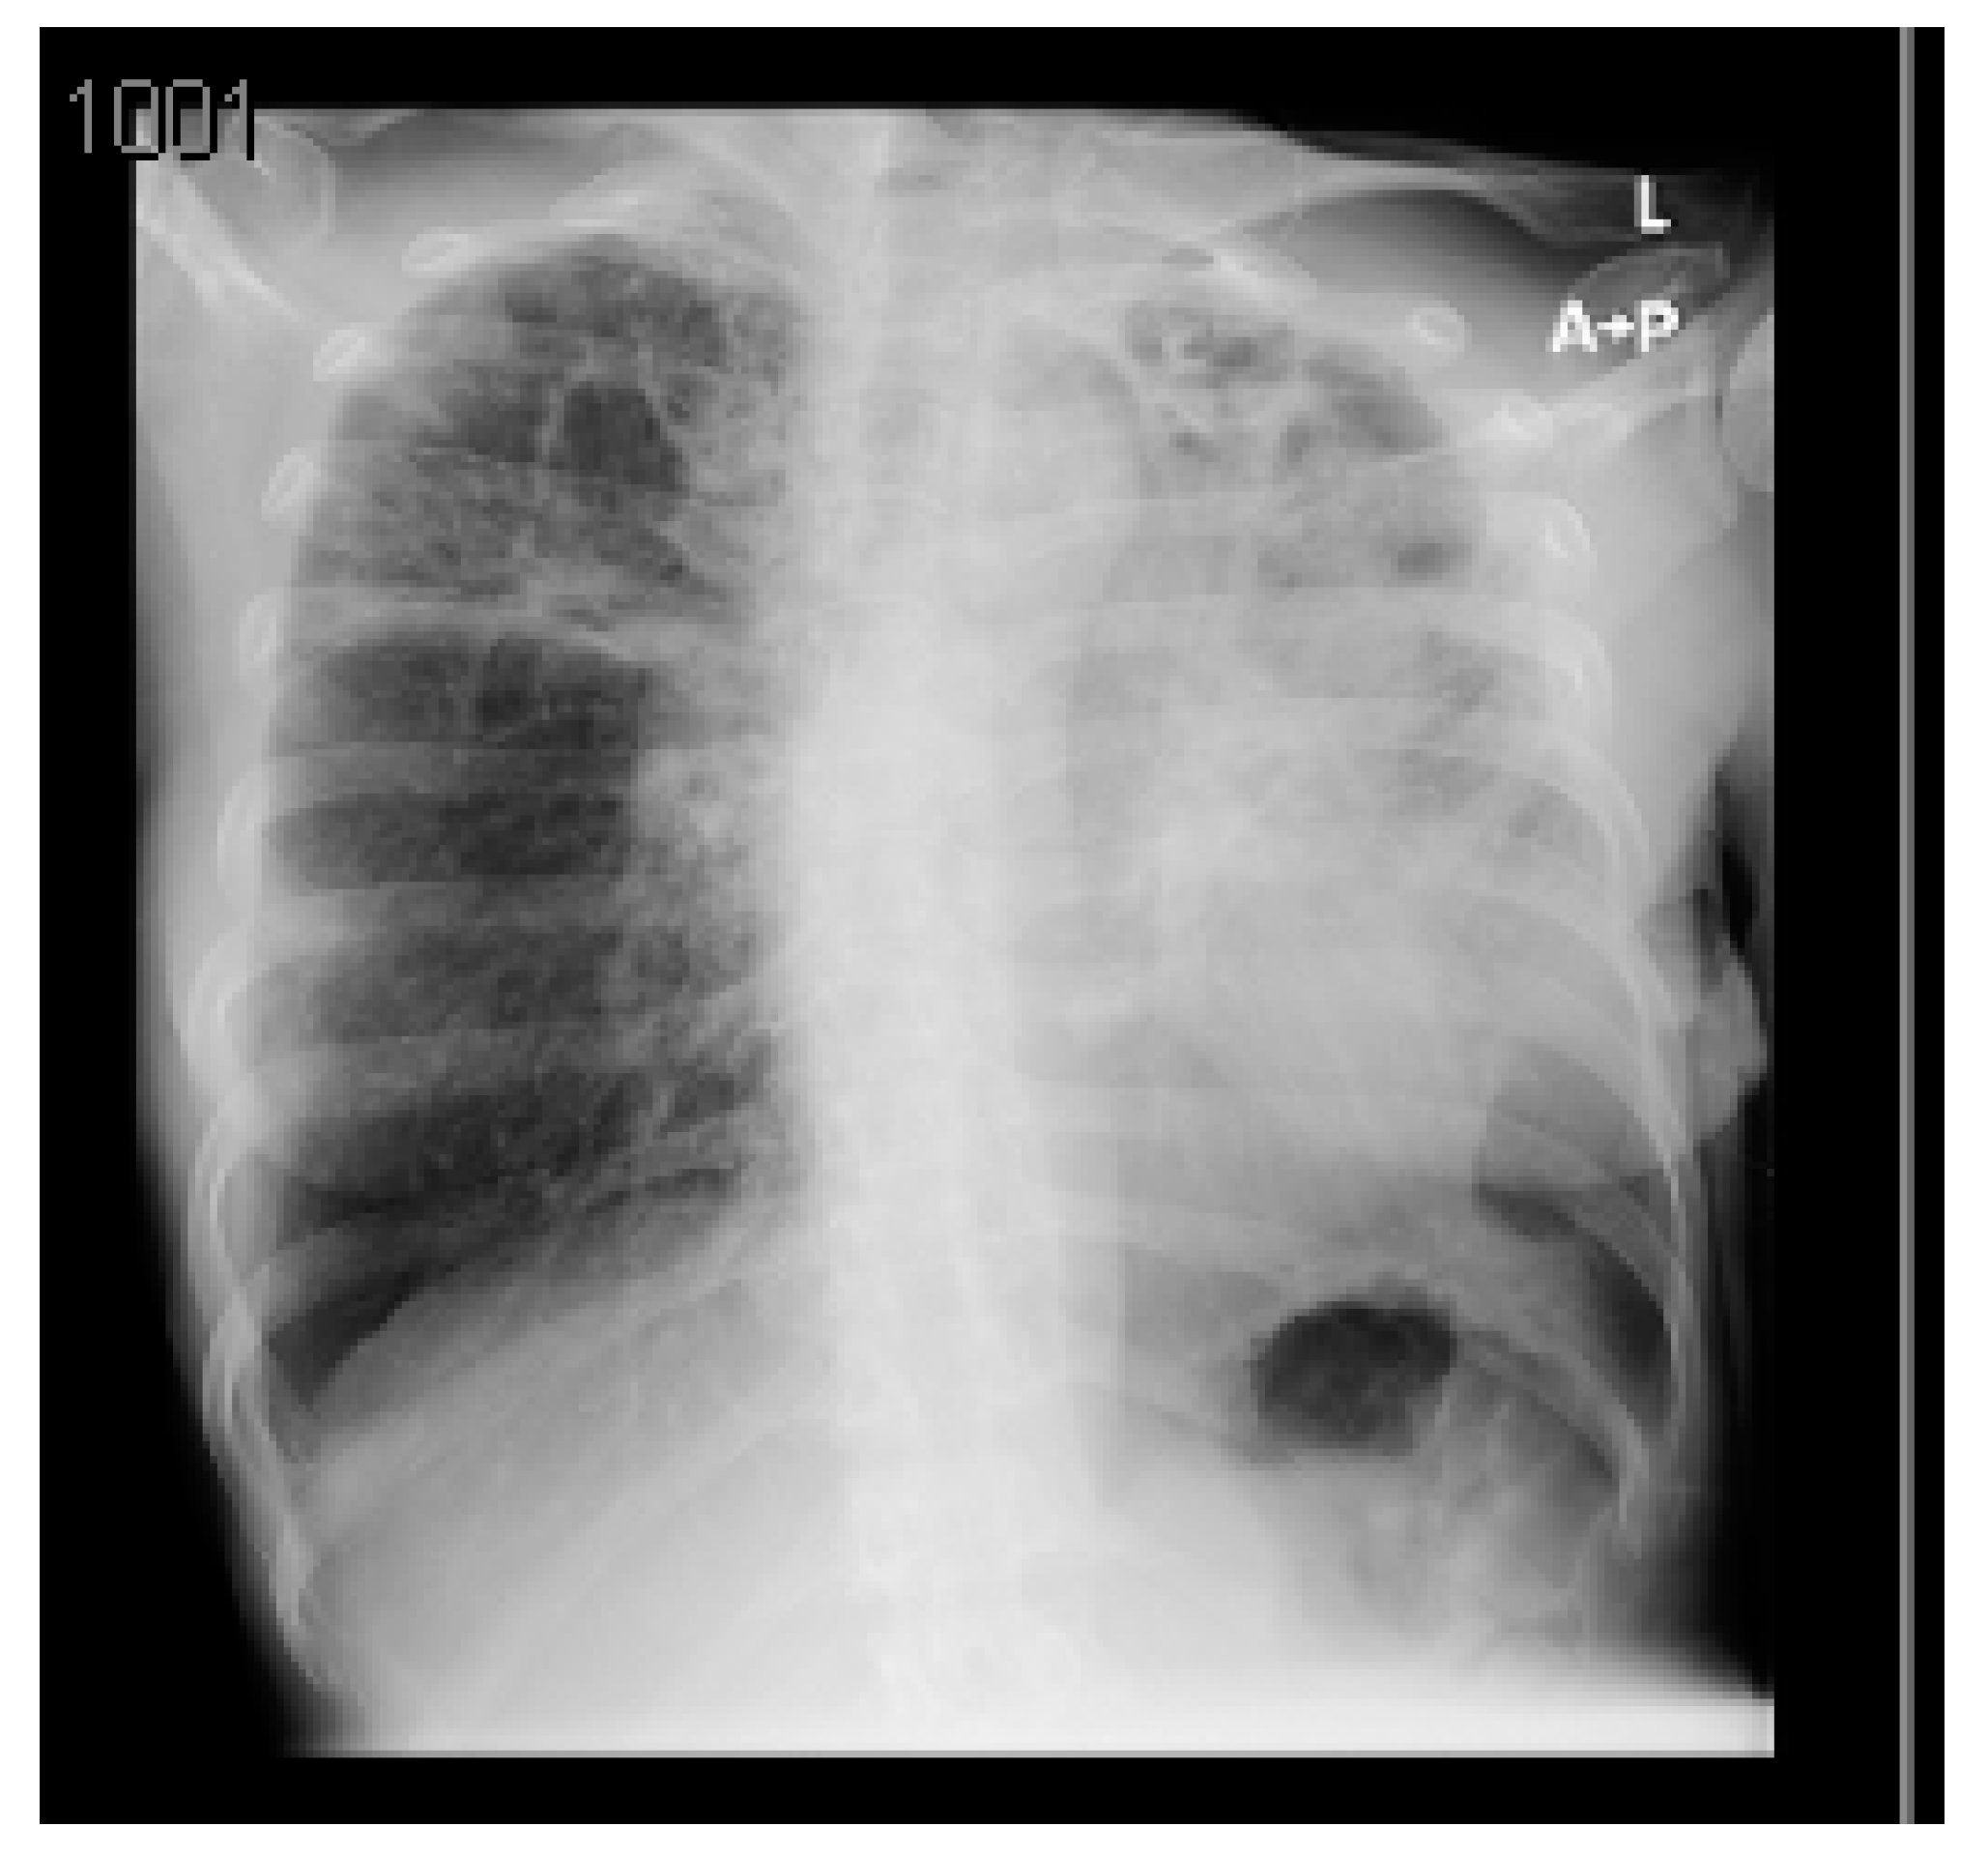

A summary of the patient’s CXR and lab investigations are demonstrated in Figure 2 and Table 2, respectively.

Figure 2. Posteroanterior chest X-ray (CXR) of the second case. The CXR demonstrates nodular changes mainly in the right lung and upper lobe of the left associated with cystic space/cavity in the upper lobe of the right lung. In addition, ill-defined consolidation with air bronchogram in the lower lobe of the right lung could be related to COVID-19. If positive otherwise, TB could not be ruled out. The cardiothoracic ratio is normal, and bilateral costophrenic angles are free with no obvious pleural effusion.